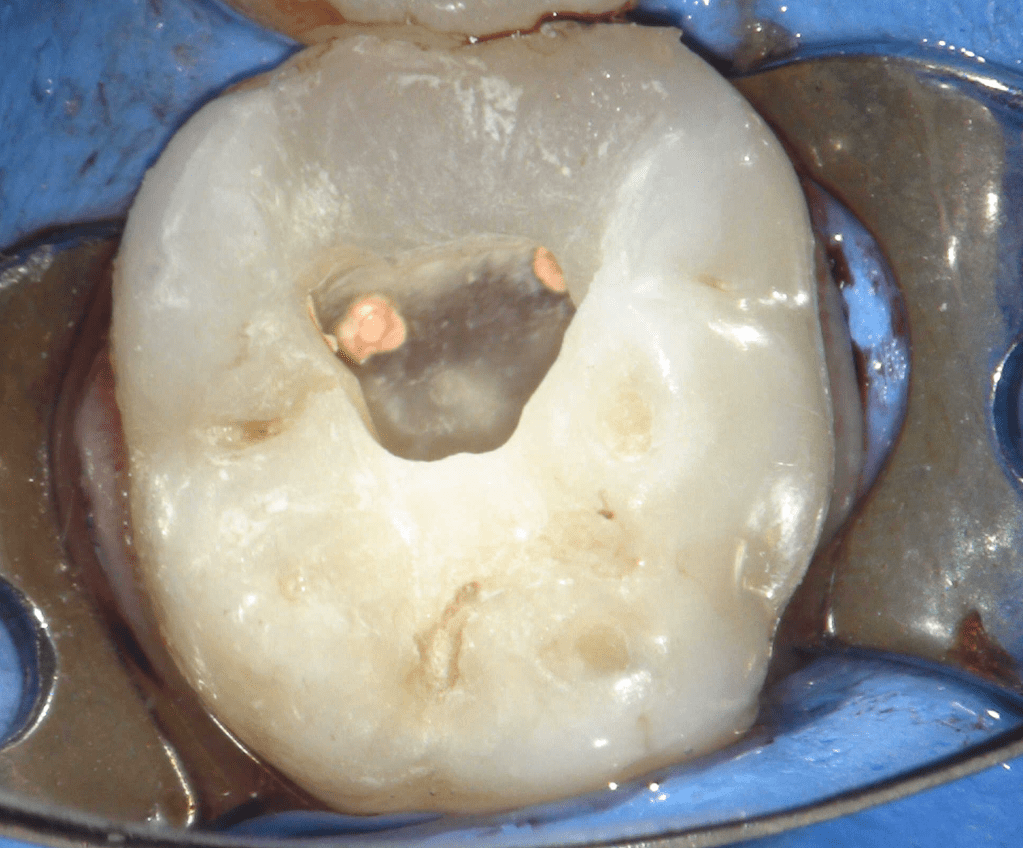

Reconstrucción preendodóntica

Reco preendo + 4 conductos molar superior